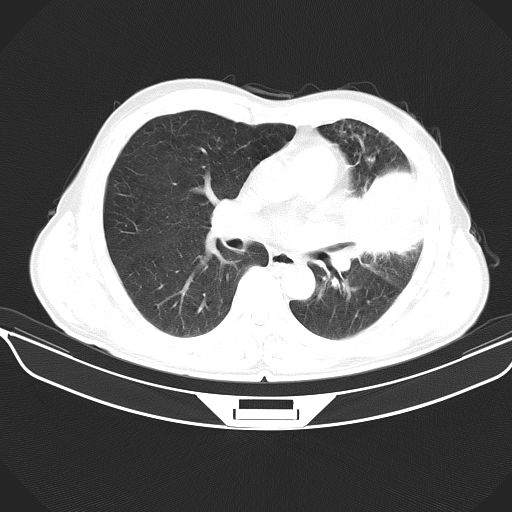

以下是引用心路寻觅在2010-3-1 10:23:00的发言:[br]1、考虑左肺上叶周围型肺癌[br]2、右上肺陈旧性病灶。[br][br][本贴已被 心路寻觅 于 2010-3-1 10:40:18 修改过]

以下是引用shuiyuan在2010-3-1 10:45:00的发言:[br]考虑左肺上叶中心型肺癌伴阻塞型炎症,邻近胸膜受侵。